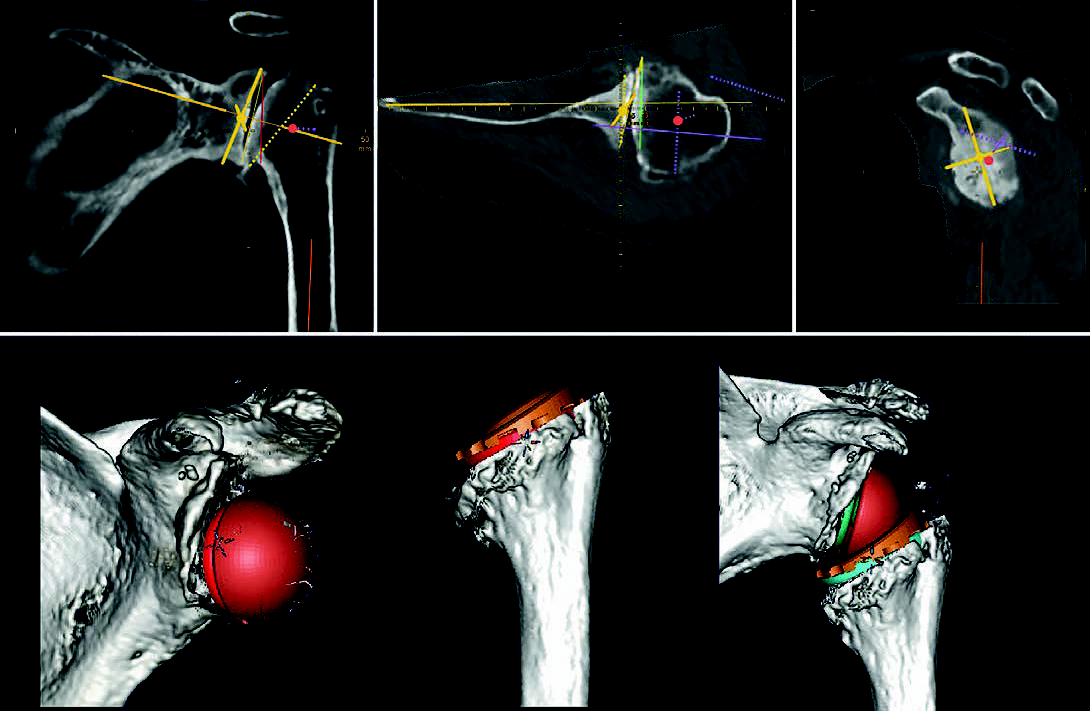

Another important point for preoperative digital planning is the successive reduction of the surgeon’s operating time, because this is a relevant part of the operation and must be included in the calculated operating time. Digital planning, like every step of an operation, has a learning curve, and with more experience this happens correspondingly faster. For example, I need between 5 and 10 minutes for normal shoulder planning. For a 3D planning with a 3D joint reconstruction including animated 3D ROM analysis and viewing of the joint from different angles, as it is currently possible with the mediCAD® Shoulder 3D software, I currently still need about 30 minutes.

mehr lesen

The 3D-reposed joint in particular, especially in the case of the inverse shoulder TEP, with a visible implanted prosthesis and the possibility of viewing it from any angle in space, is currently still something exciting new for me with many variables that are still possible. Currently, I am trying to figure these out in a playful way to find the previously known optimal prosthesis position, check it against new possibilities and validate it, ideally taking into account soft tissue stress ratios due to length changes. In the beginning, I needed an hour for the same planning steps, now, as already mentioned, it is 30 minutes, i.e. the learning curve shows that here, too, the pure planning time is reduced with increasing experience, with even better results.

The shoulder joint, like every joint in the body, consists of two joint partners moving against each other, which are

are connected by soft tissues and only certain sizes and positions of the joint replacement ensure, even after surgery, the regular, satisfactory for the patient, long-term function. If it is possible today with the

mediCAD® animated 3D joint planning with ROM analysis, there is nothing more obvious to me than to simulate and test these optimal prosthesis sizes and their alignment, including the possible technical freedom of movement from a bony and implant-related point of view, in advance and without the risk of surgery.

in advance without any surgical risk. Then I can go into the operation relaxed and with a clear concept and a good conscience towards the patient.

The automatic bone segmentation

Another advantage of mediCAD® Shoulder 3D is that the surgeon himself (and not some engineer of the implant manufacturer) can perform the segmentation of the CT data set according to his medical experience and interpretation of the CT images. In addition, the creation of a 3D model and the possibility of subsequent planning of the glenoid and humerus individually one after the other are possible. Also, full joint planning after reduction of the joint with implanted components are features that I, as a physician, would not want to miss. And of course the 3D ROM analysis of the reduced joint with the prosthesis in place.